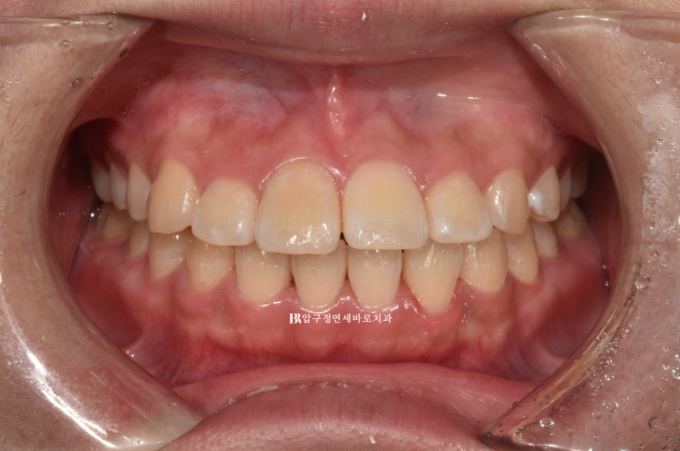

23.04

10년 전 어릴때 비발치 교정을 했던 환자분입니다.

치아는 가지런하고 어금니도 잘 씹히는데 재교정을 안하는 이유는

앞니뻗침 때문이었습니다.